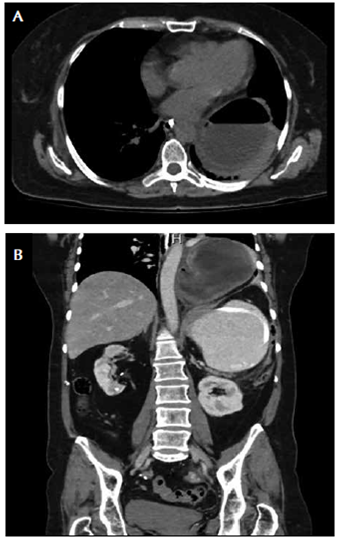

La concentración de la lipasa fue normal. En la TC de abdomen se observó una colección de 95 x 95 mm, con paredes bien definidas, morfología redondeada y contenido hidroaéreo, en la base del hemitórax izquierdo, aparentemente, de localización en el mediastino y extrapulmonar, no dependiente de la pleura, asociada con importante dilatación y aparente obstrucción del estómago a la altura del antro (figura 3, A y B).

Figura 3 A. TC axial: hemitórax izquierdo ocupado por parte del estómago, el cual se encuentra dilatado y contiene un nivel hidroaéreo. B. Hernia hiatal de tipo III: estómago en ‘reloj de arena’, herniado y con vólvulo, que ocupa la base del hemitórax izquierdo.